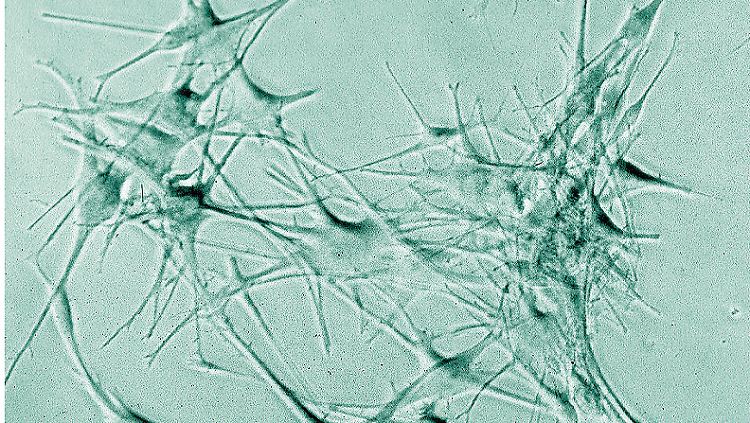

Ohne sie geht's nicht: Dendritische Zellen sind Teil des Immunsystems. Sie erkennen Fremdkörper und geben eine entsprechende Botschaft an die Killerzellen weiter.

(Foto: Fraunhofer IGB)

Eine Untergruppe des tierischen Immunsystems, die dendritischen Zellen, wanderte auf das Alarmsignal hin zu der Scheibe, gelangte in ihre feinen Gänge und traf dort auf die Tumor-Bestandteile. Damit hatte das Team den ersten Erfolg erzielt: dendritische Zellen sind wichtige Boten. Sie finden und erkennen Fremdkörper, wandern zu den Lymphknoten und geben ihre Information dort an Killerzellen weiter. Diese wissen fortan, wonach sie suchen und was es zu bekämpfen gilt – in diesem Fall: Tumore.